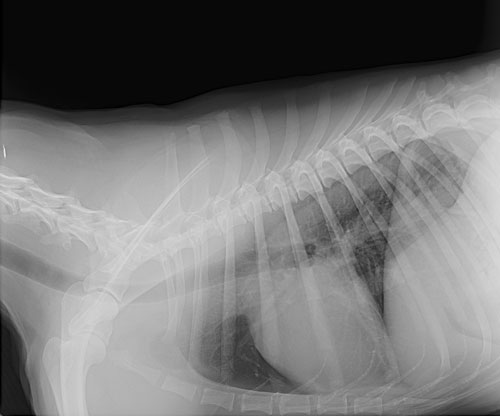

When an examination and lab results are not enough to find a proper diagnosis, we offer digital x-rays and ultrasound services in house, with a radiologist/ultrasound referral to grasp at what we can’t see on the outside, including bones and internal organs.